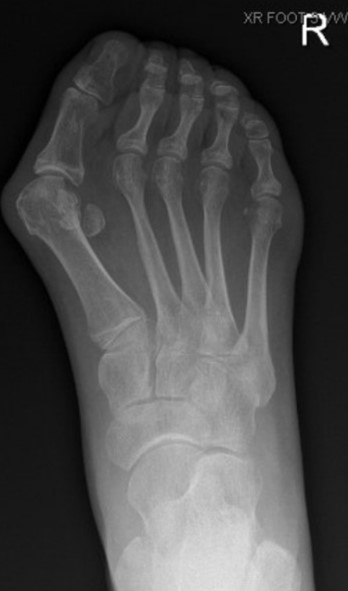

post-operative bunion correction

Figure 3: post-operative bunion

correction using Akin and Chevron osteotomies

Akin Osteotomy

Akin osteotomy corrects the sideways deviation of the big toe. In this procedure, your surgeon makes a small cut in the proximal phalanx (base of the big toe) and removes a wedge of bone to straighten the big toe. The bony fragments are then stabilized using a screw. This procedure is often used in conjunction with the other procedures below.

Chevron Osteotomy

A chevron osteotomy is usually recommended for mild to moderate bunion deformities. During this procedure, your surgeon will make an incision over your big toe. The joint capsule is opened, and the bunion is removed using a surgical saw. A V-shaped cut is made on your big toe and the metatarsal bones are shifted to bring your toe into its normal anatomical position. The bunion is then shaved and the soft tissues are realigned into the correct position. Akin osteotomy may be performed if necessary. The mobility of your big toe is examined, and the capsule and wound are re-approximated with sutures. Screws are used to hold the bones in their new position until healing.